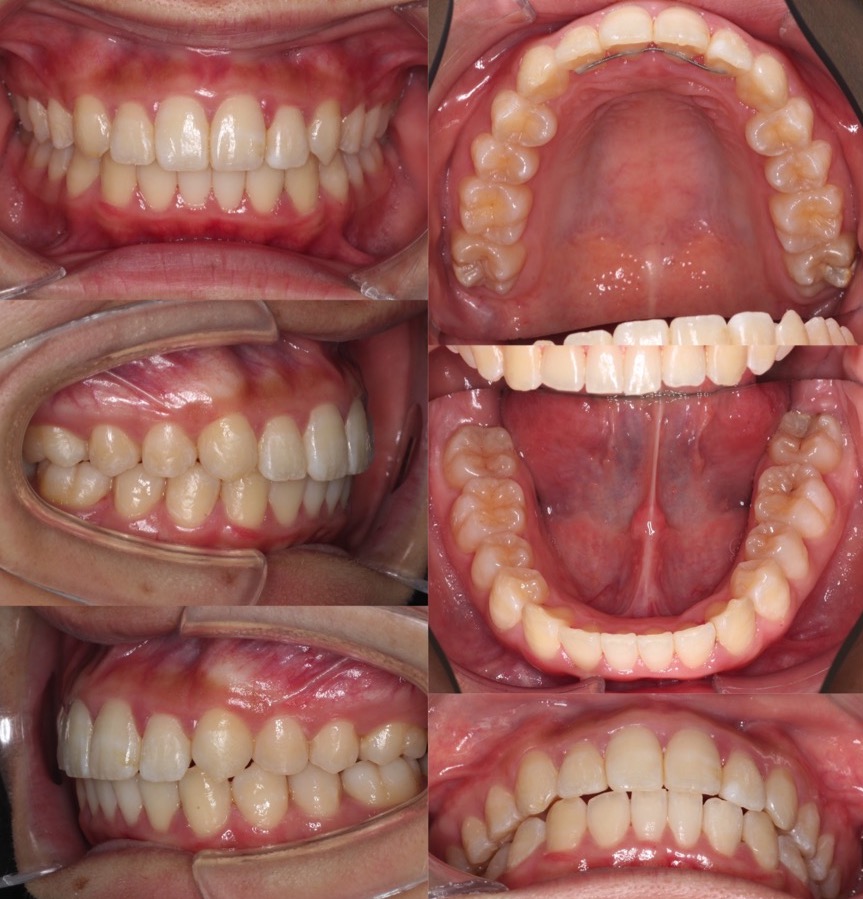

高校生女性・唇側矯正装置・上抜歯

上の前歯が前に出ているため下唇に当たり口が閉じづらいという症状を、抜歯を併用して前歯を引っ込めて治しました。術後は奥歯を含めて理想的なかみ合わせになり、スマイルも大きく変化しました。ご本人からも大変満足していただけました。少し前歯が小さめですが、唇側矯正装置であればしっかりと歯の動きをコントロールする事ができます。

<症例概要> 難易度★★★☆☆

主訴:出っ歯

年齢・性別:高校生女性

住まい:千葉県船橋市

症状:上顎前突・叢生・過蓋咬合・右側シザースバイト

治療方針:上抜歯空隙閉鎖(中等度固定)・ストリッピング

治療装置:唇側矯正装置

固定装置:ナンスホールディングアーチ

抜歯:上第一小臼歯(計2本)

治療期間:2年2か月

リテーナー:上プレートタイプ+クリアタイプ・下フィックスタイプ

治療費用:968,000(税込)

代表的副作用:痛み・治療後の後戻り・歯根吸収・歯髄壊死・歯肉退縮

▶︎その他の副作用